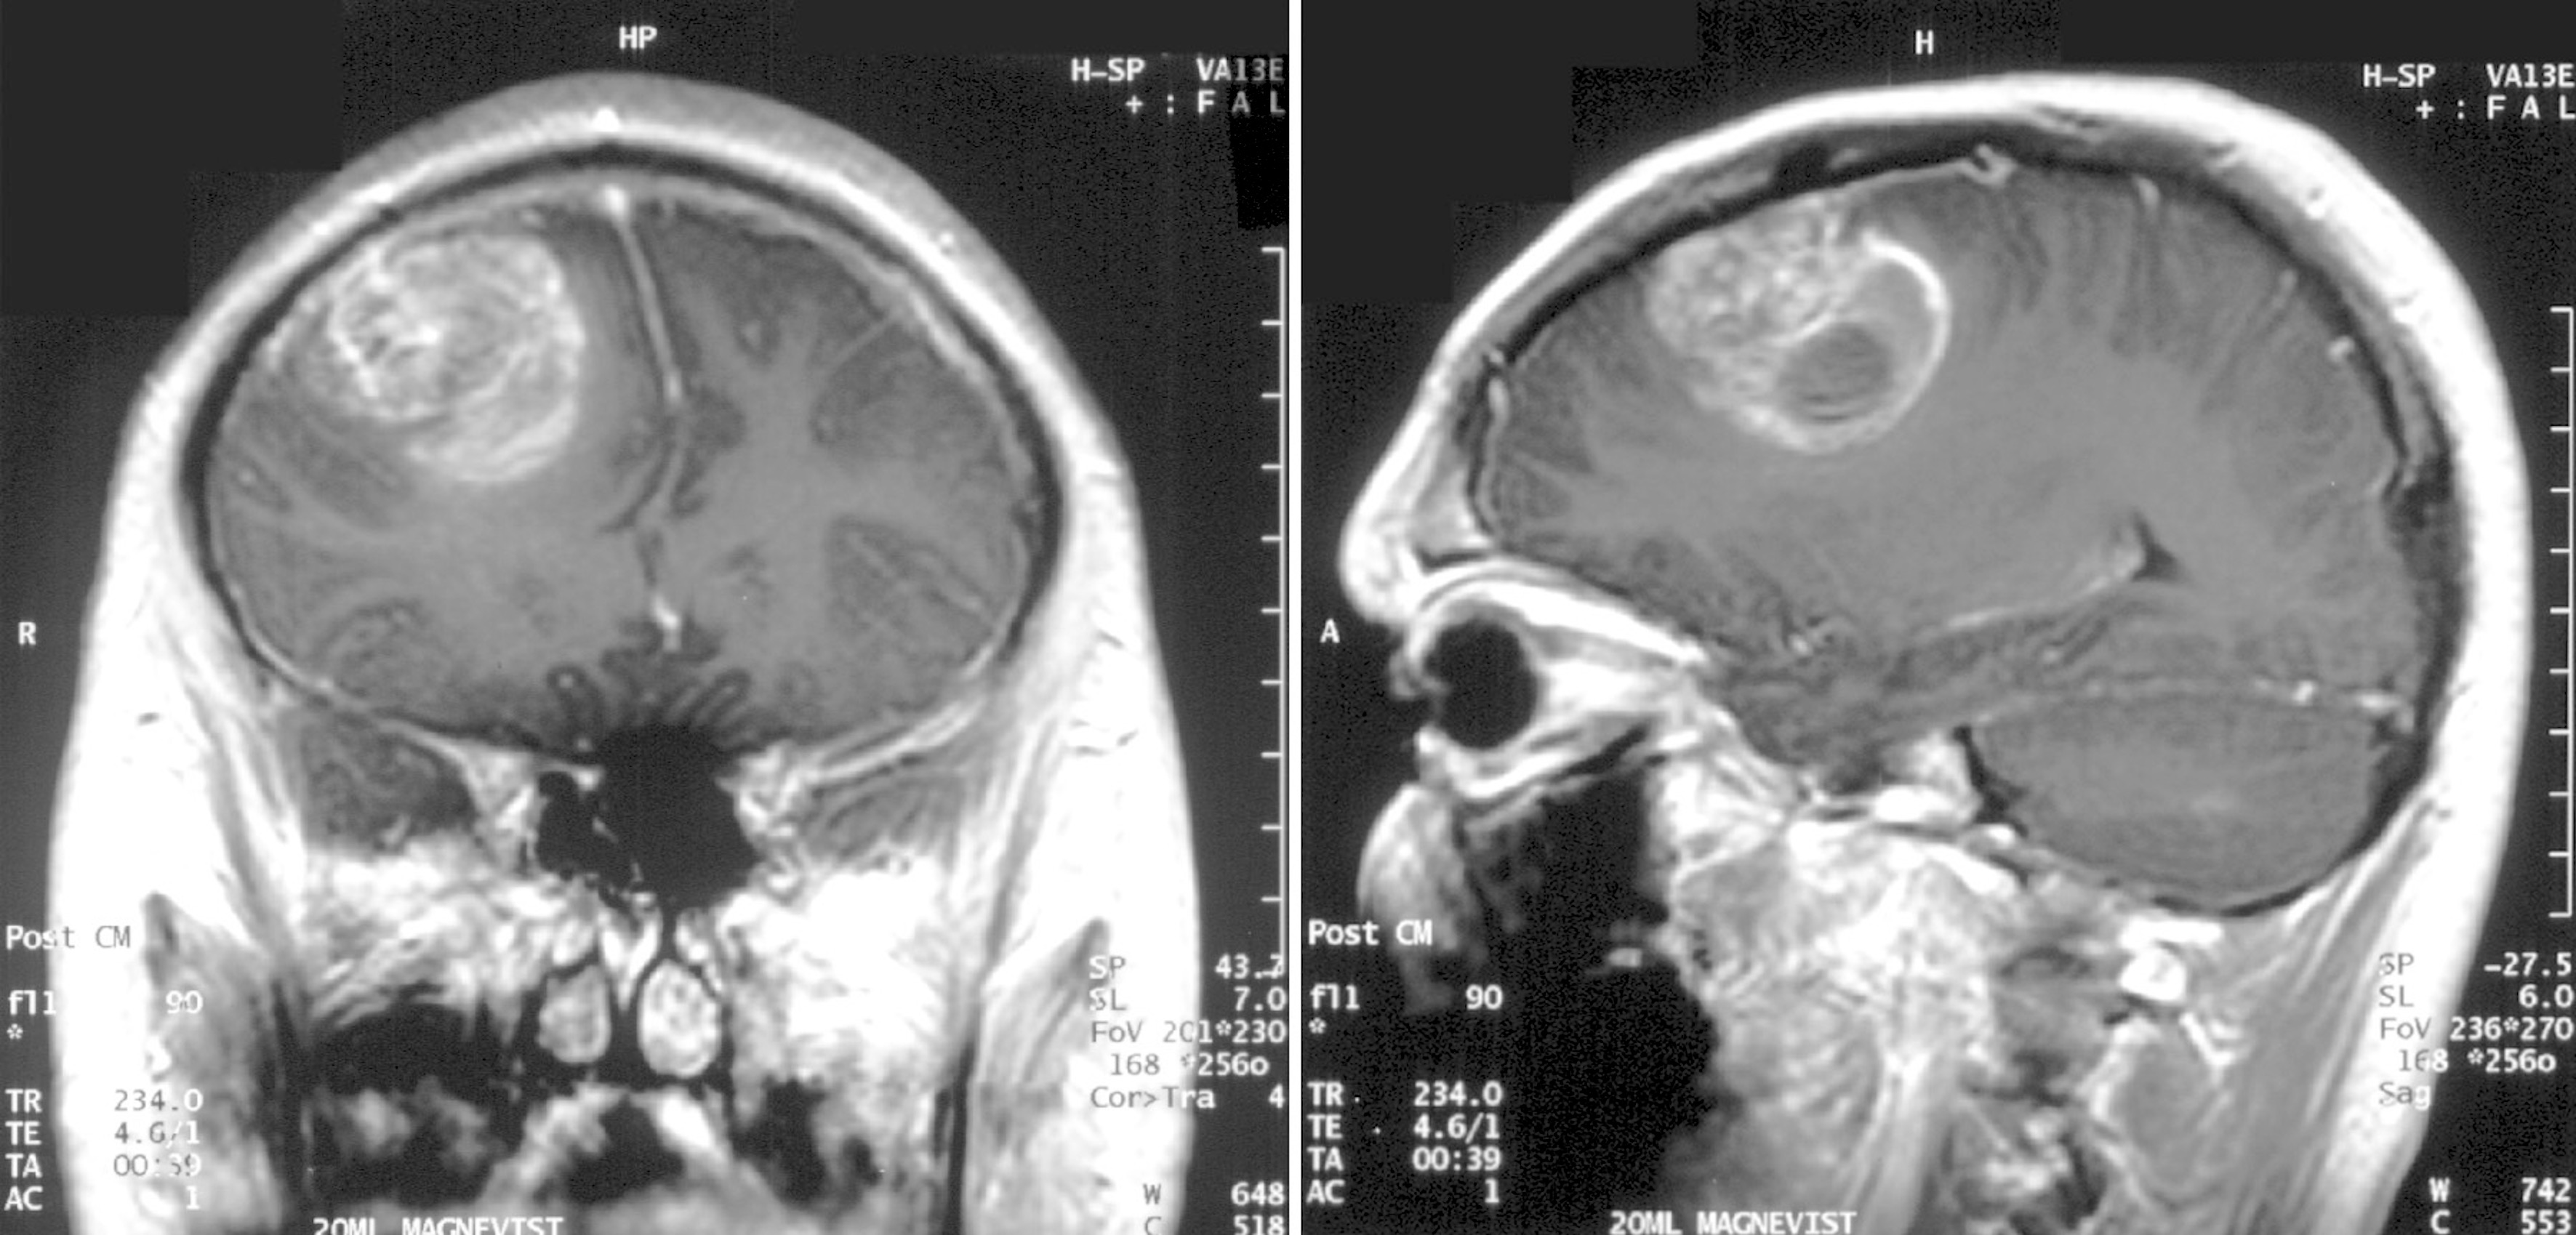

一名15岁男孩的多形性胶质母细胞瘤核磁共振(MRI)影像

(资料来源/Wikimedia Commons)